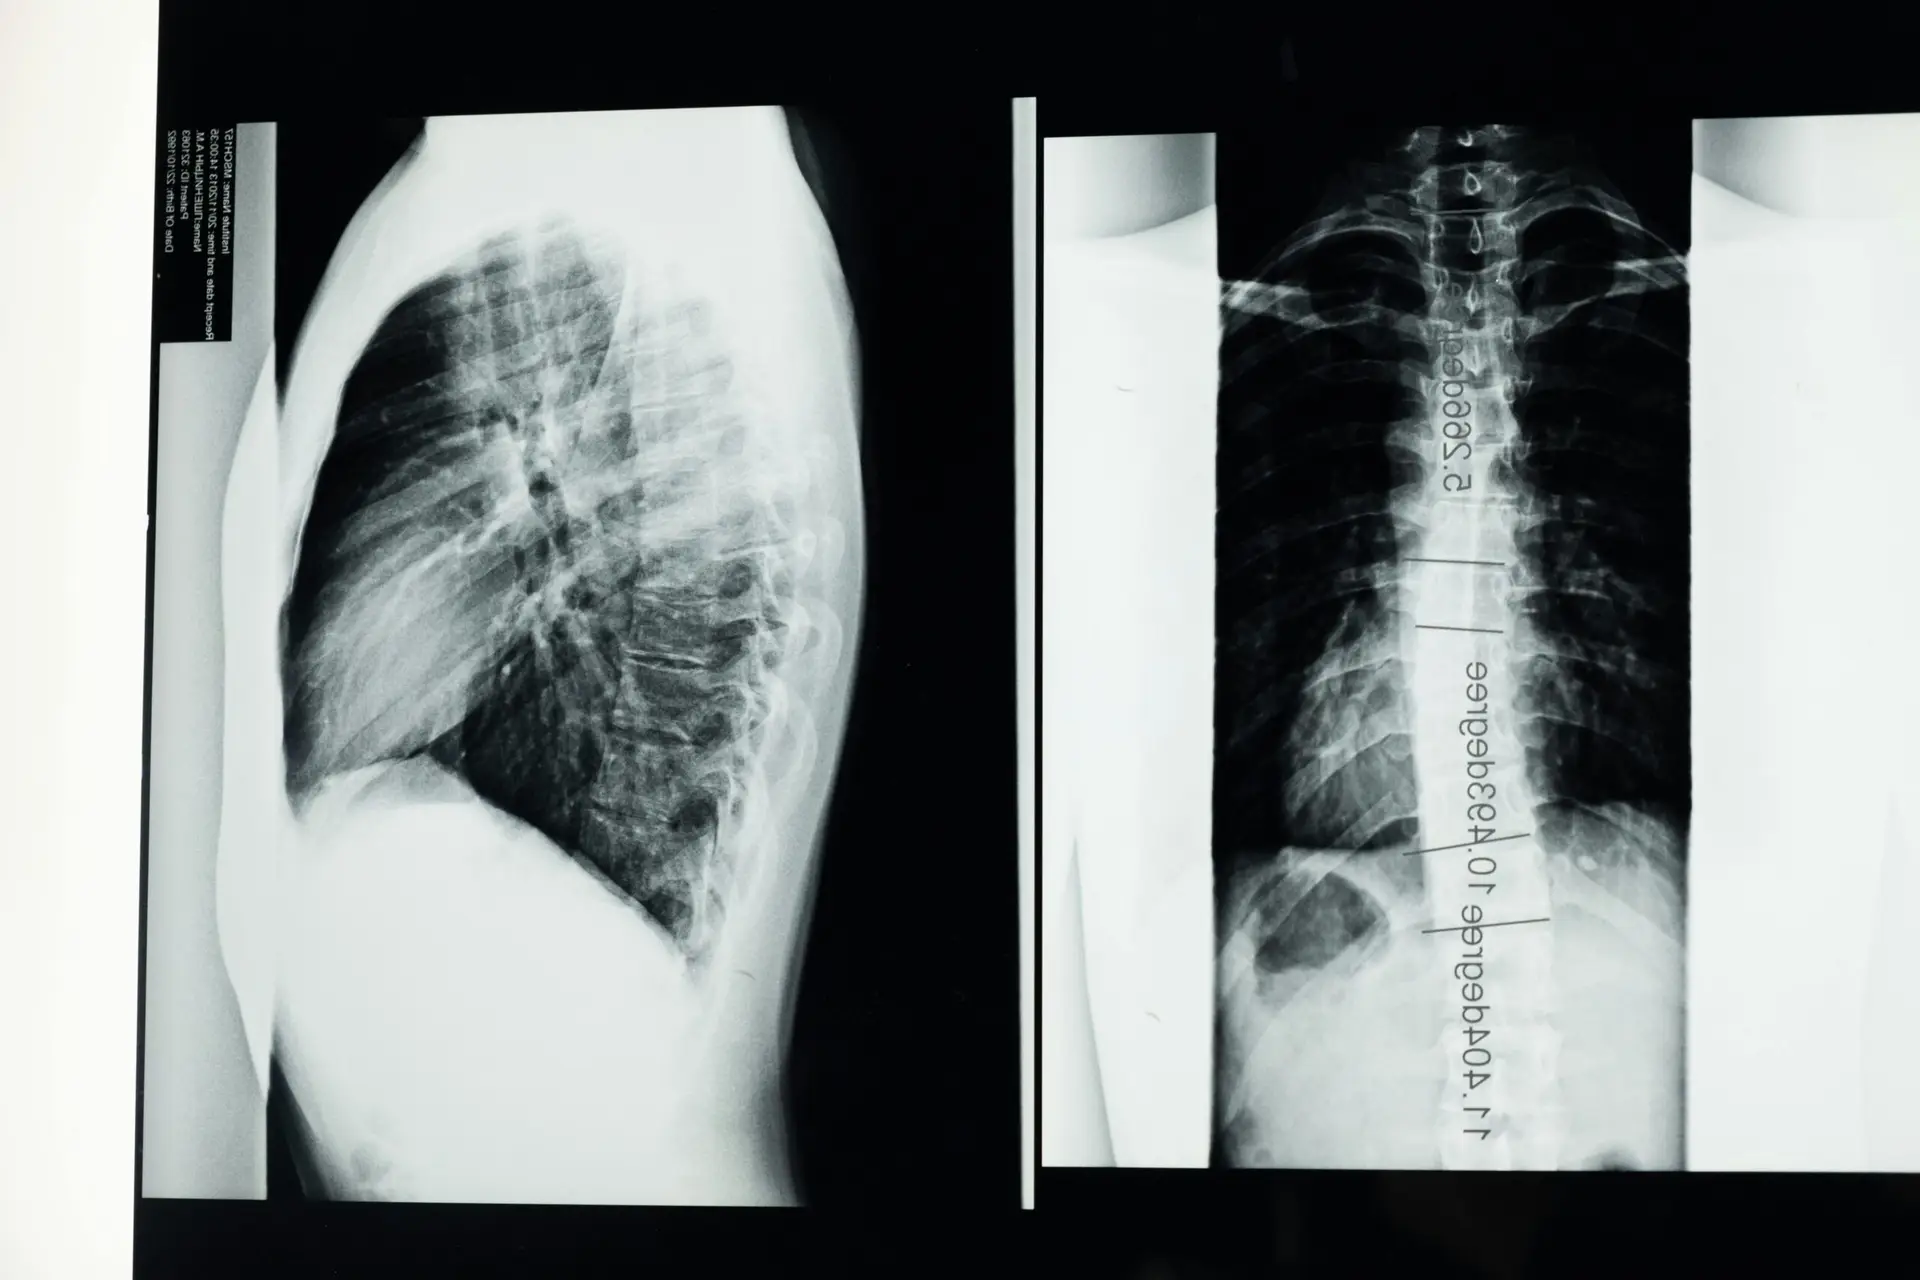

Best Scoliosis Doctor Sarasota: If you’re searching for the best scoliosis doctor in Sarasota, you’re likely wading through a sea of opinions, options, and acronyms—PT, CBT, TLSO, EOS, ADLs, and more. You’re also probably wondering which path actually helps you...